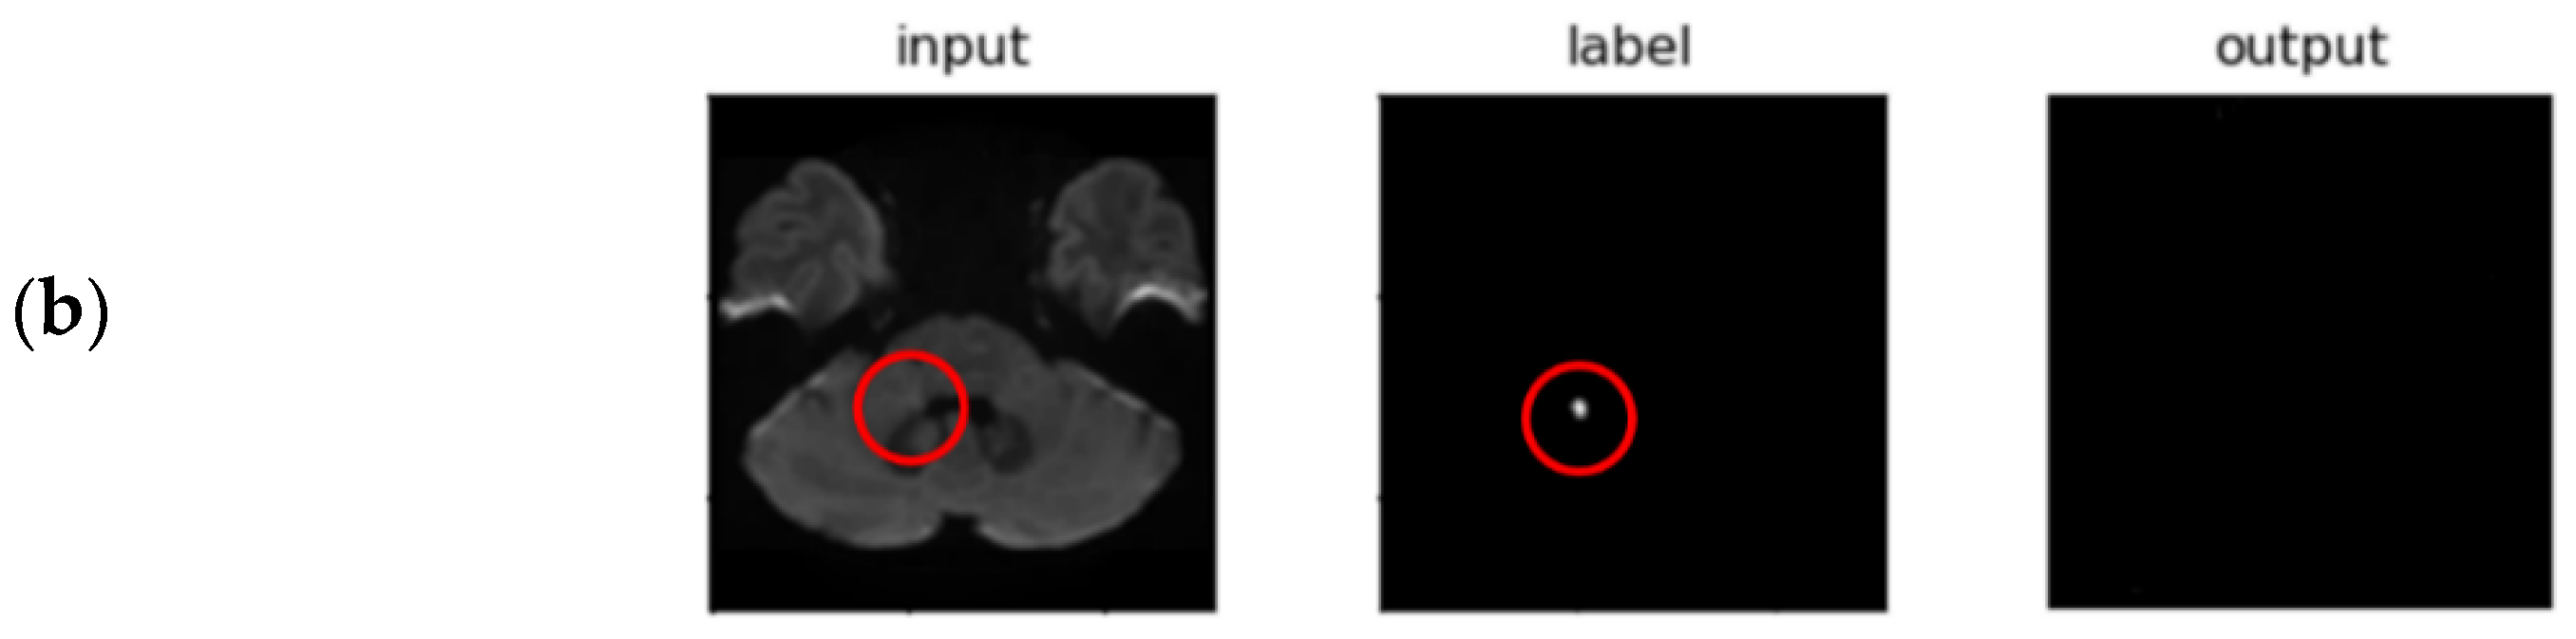

3.2. Segmentation Performance